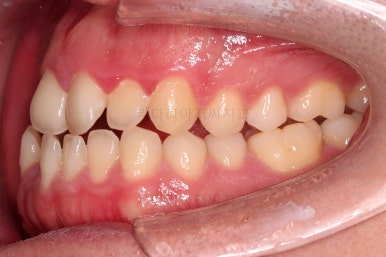

수술 전 교정과정이 거의 마무리 되어 갑니다.

오히려 앞니가 거꾸로 물리는 정도는 더 심해지고요.

수술 직전이 얼굴모습도 가장 주걱턱이 심한 양상으로 됩니다.

수술 전 교정 7개월 -> 수술 및 회복 1개월 -> 수술 후 교정 7개월

이 정도 스케쥴로 부산긴얼굴긴턱교정 이번 환자분은 진행되었는데요.